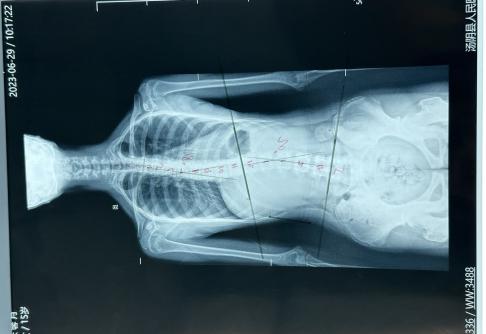

脊柱侧弯:又称脊柱侧凸,是指脊柱一个或数个节段因某种因素向冠状轴上偏离中心线和矢状面上后凸或前凸的增加和减少的脊柱弯曲异常,是一种三维畸形[1]。目前被广泛采用标准是脊柱正位X线片Cobb’s角≥10°,即可诊断脊柱侧弯。该病发病原因、发病机制尚不明确。大致可分为先天性、后天性两种。先天性脊柱侧弯多是由于脊柱及其附属结构发育异常导致。后天性脊柱侧弯可因姿势不良、病理性脊柱异常引发。80%的脊柱侧弯病因不明,好发于青少年,女性多见,医学上称之为青少年特发性脊柱侧弯,可能和遗传、激素、神经内分泌系统异常等原因有关。因其起始一般比较隐蔽,早期没有任何不适,脊柱侧弯往往容易被忽视。患者一般在11-17岁期间(青春期)侧弯发展加速,严重的结构性侧弯逐渐形成,18-20岁侧弯发展相对稳定,最终给患者家庭沉重的经济负担。

在家自测出现问题,家长不要慌,来医院查脊柱全长片进行确诊。康复科医生根据全长片测量Cobb’s角。

医生根据Cobb’s角的大小,脊柱侧弯的弧度和类型不同进行个体化的治疗方案。